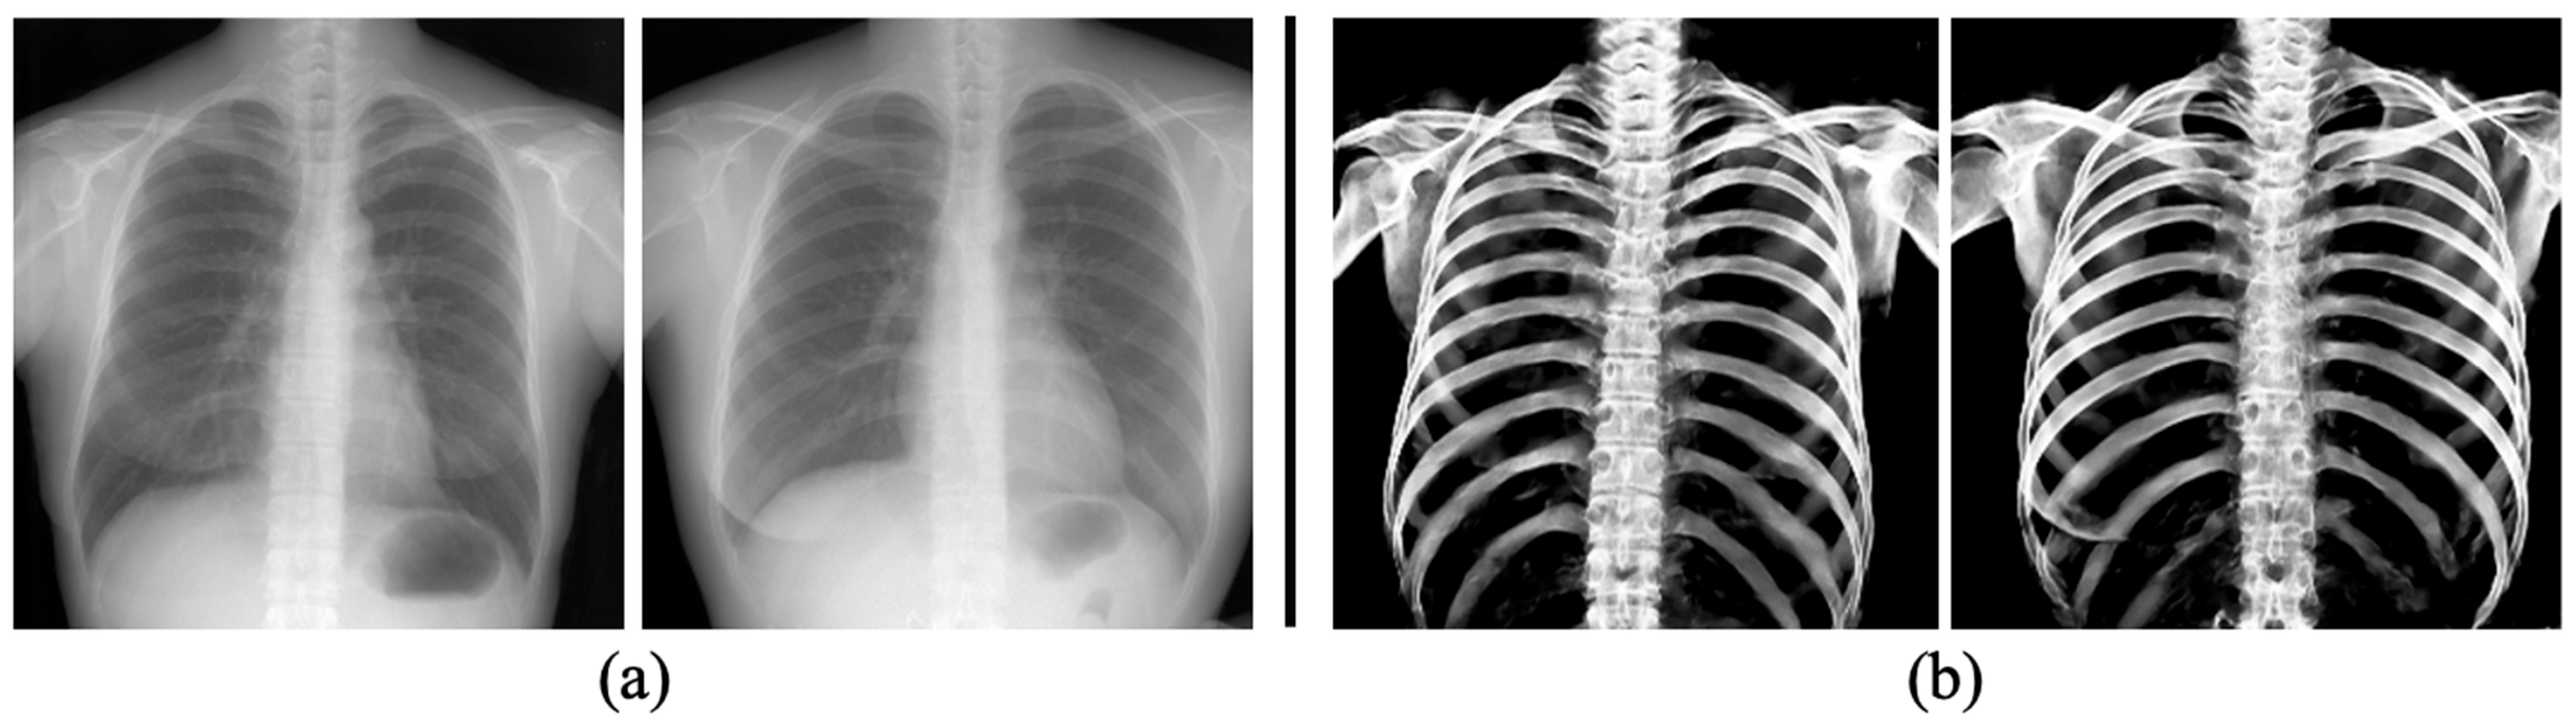

3.3. The Performance of Bone Extraction on Real 2D X-ray Images (CXRs)